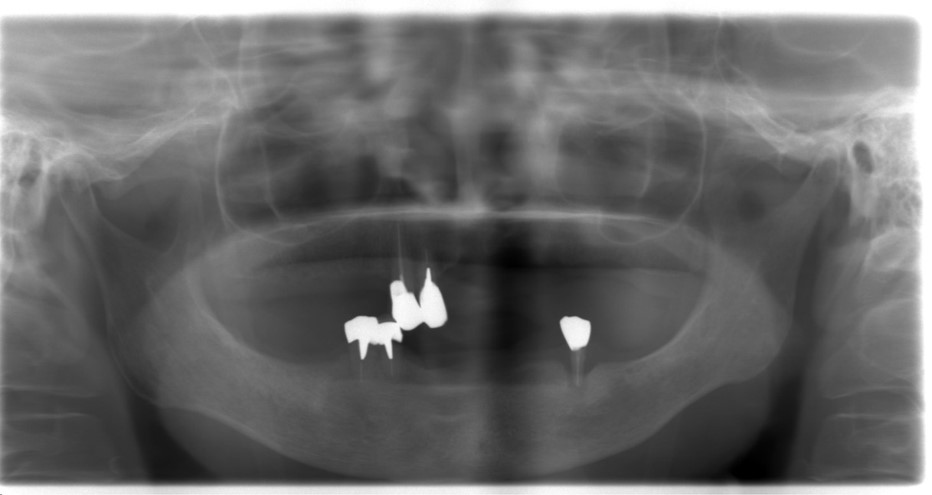

インプラント手術計画(CT)

使用中の治療義歯のデジタルデータとCTデータを重ね合わせました。

こうすることで、アタッチメントが理想的な位置関係になるようインプラントの手術計画を立てました。